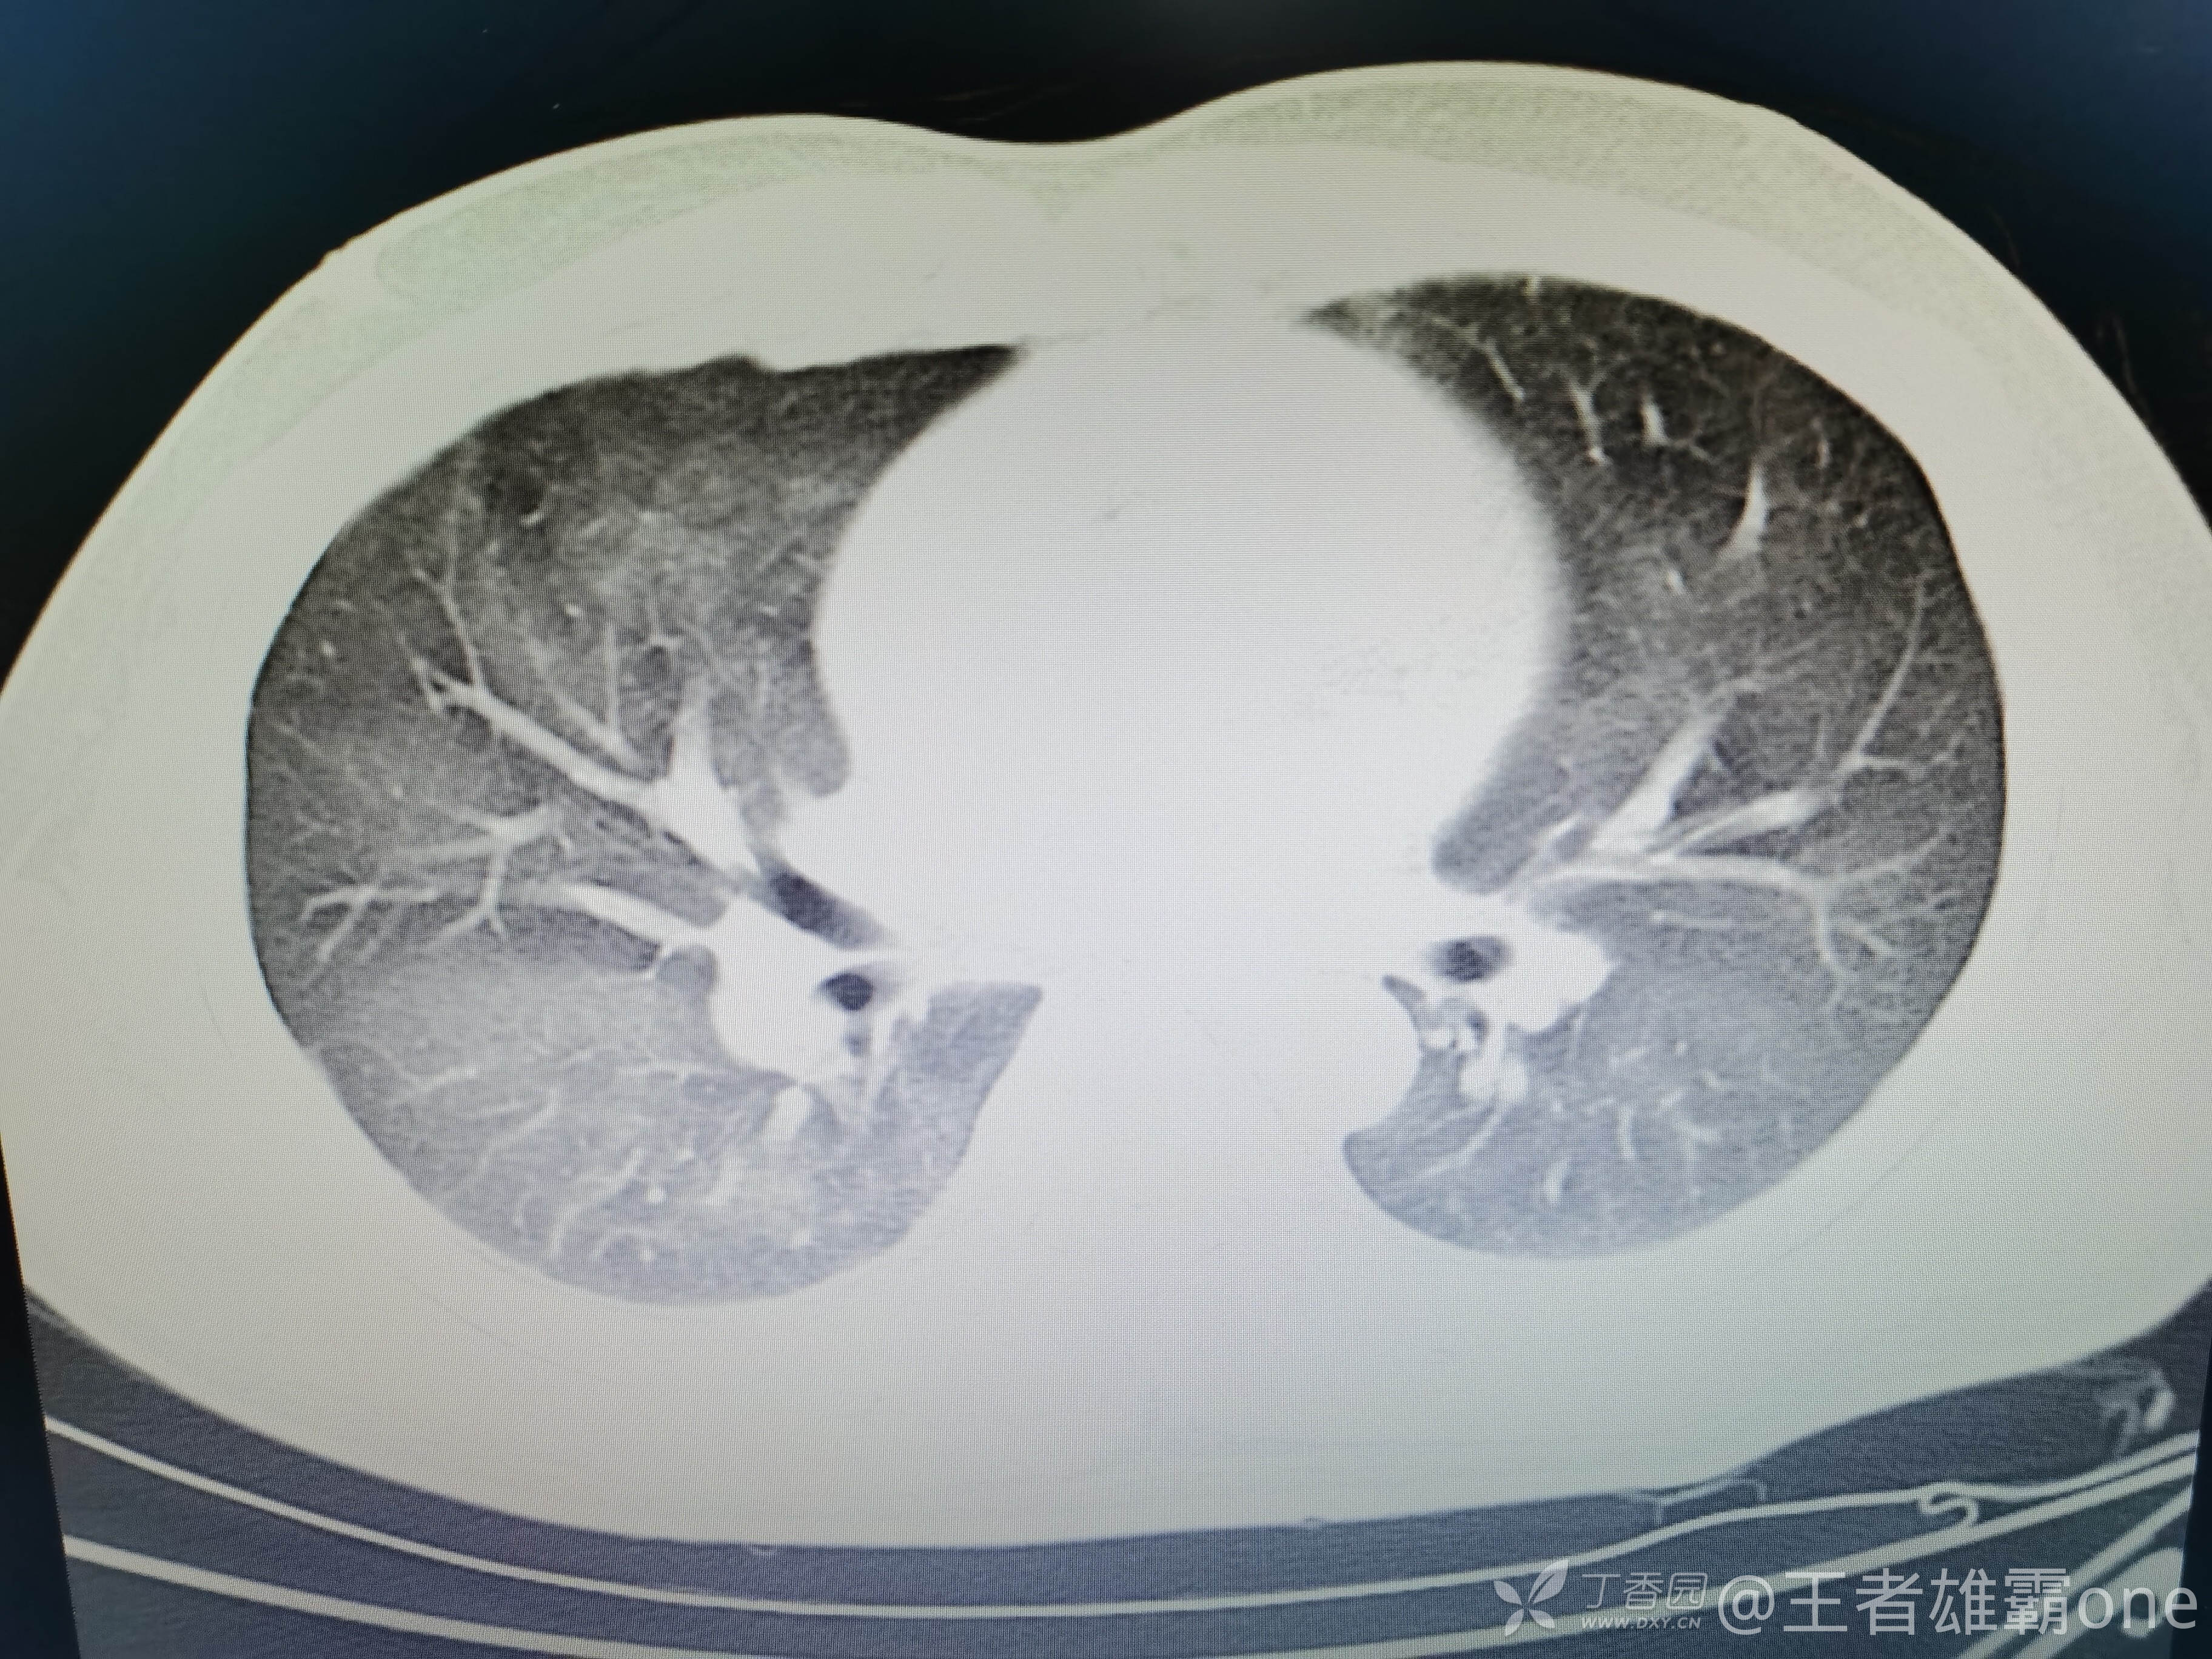

西门开心 推荐男,33岁,否认既往有心脏基础疾病,6-1受伤后急诊行右胫腓骨骨折固定术(术前胸部CT无明显异常,见后面视频前半部分),术后逐渐出现刺激性咳嗽、胸闷,无精神症状,无皮疹,无胸痛,无咯血等。6-6完善胸部CT、脑钠肽前体、心超等辅查,其中脑钠肽前体、心超无明显异常。复查的胸部CT见视频后半部分:

附几张CT图片: